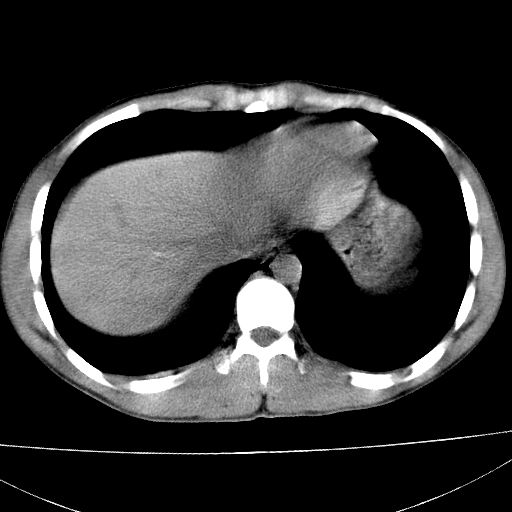

标题: CT15860:男,21岁,腹部外伤2小时伴胸疼。 [打印本页]

标题: CT15860:男,21岁,腹部外伤2小时伴胸疼。

b超示:肝破裂。

肝脏及肾脏明显有损伤性改变并激发腹腔内积液(血),以肝脏撕裂及肾周积血显著。

1)肝破裂伴腹腔积液(血)。2)右肾破裂伴右肾包膜下及肾周血肿。3)腹部空腔脏器穿孔可能。4)右侧少量胸腔积液(血)。